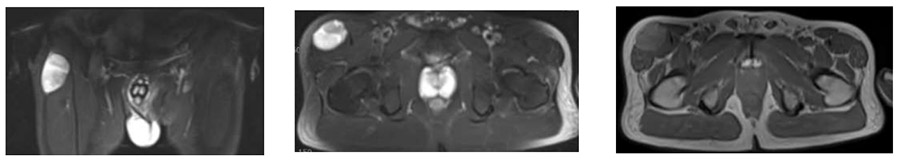

İlk Başvuru: İlk ameliyat öncesi MR’da uyluk üst ön kısımda heterojen yumuşak doku kitlesi görülmekte

Ameliyat Öncesi: İlk ameliyat sonrası MR’da uyluk üst ön kısımda kalıntı tümör dokusu ve çevreleyen ödem, PET_CT’de minimal artmış aktivite görülmekte